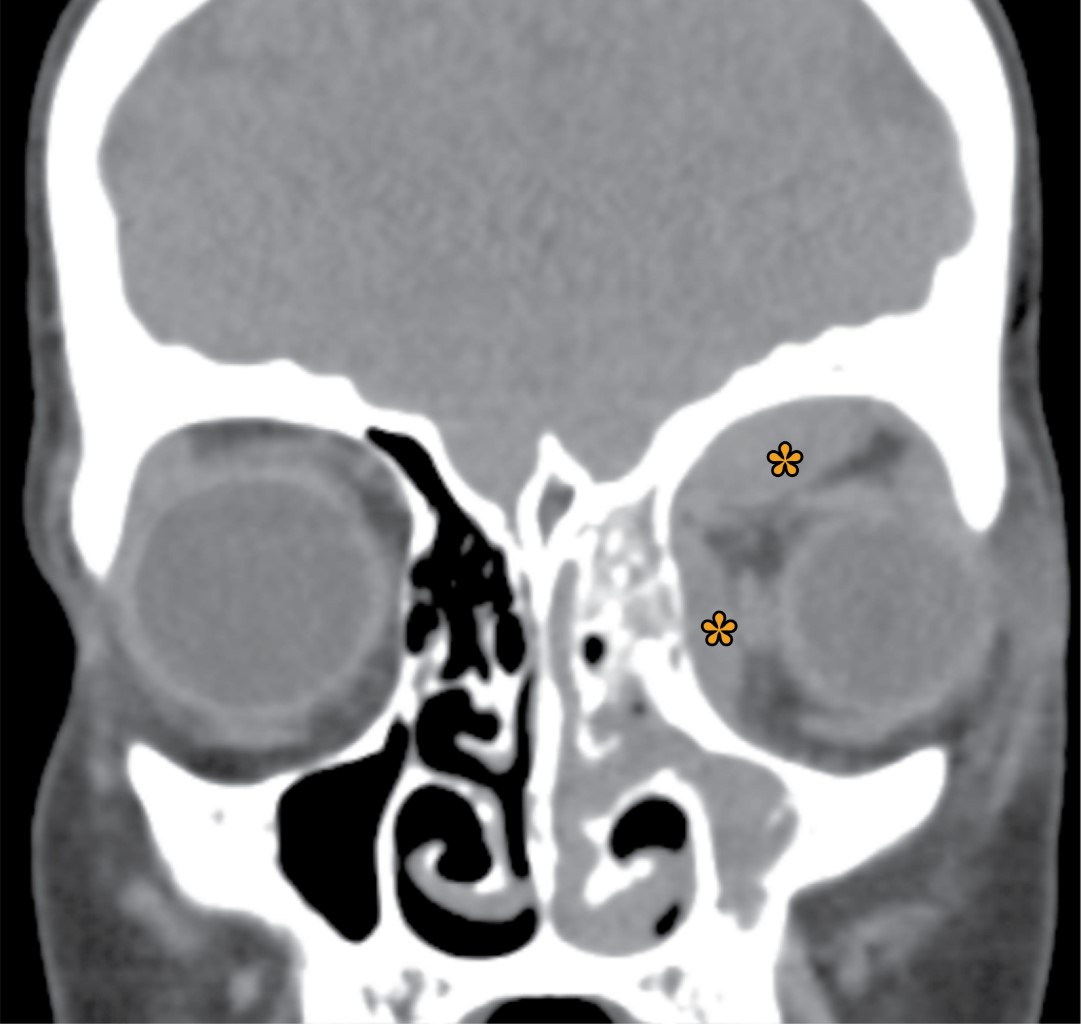

Orbital cellulitis secondary to sinusitis due to Prevotella loescheii

Orbital cellulitis is a potentially serious entity characterized by the presence of proptosis, ocular pain, limitation of ocular movements and decreased visual acuity. Given the location of the infection and the possibility of sequelae, early and intensive management is essential. In the following article we describe a case of an 13-year-old adolescent who presented with orbital cellulitis secondary to sinusitis due to Prevotella loescheii. He required intravenous antibiotherapy and surgical intervention for drainage, with good clinical evolution.

Figure 2